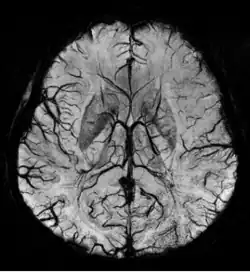

Susceptibility weighted imaging (SWI), originally called BOLD venographic imaging, is an MRI sequence that is exquisitely sensitive to venous blood, hemorrhage and iron storage. SWI uses a fully flow compensated, long echo, gradient recalled echo (GRE) pulse sequence to acquire images. This method exploits the susceptibility differences between tissues and uses the phase image to detect these differences. The magnitude and phase data are combined to produce an enhanced contrast magnitude image. The imaging of venous blood with SWI is a blood-oxygen-level dependent (BOLD) technique which is why it was (and is sometimes still) referred to as BOLD venography. Due to its sensitivity to venous blood SWI is commonly used in traumatic brain injuries (TBI) and for high resolution brain venographies but has many other clinical applications. SWI is offered as a clinical package by Philips and Siemens but can be run on any manufacturer's machine at field strengths of 1.0 T, 1.5 T, 3.0 T and higher.

SWI uses a fully velocity compensated, RF spoiled, high-resolution, 3D gradient recalled echo (GRE) scan. Both the magnitude and phase images are saved, and the phase image is high pass (HP) filtered to remove unwanted artifacts. The magnitude image is then combined with the phase image to create an enhanced contrast magnitude image referred to as the susceptibility weighted (SW) image. It is also common to create minimum intensity projections (mIP) over 8 to 10 mm to better visualize vein connectivity. In this way four sets of images are generated, the original magnitude, HP filtered phase, susceptibility weighted, and mIPs over the susceptibility weighted images.